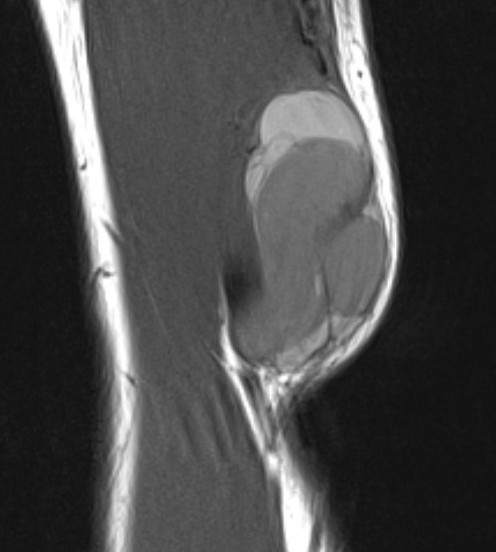

MRI

Heterogenous mass, low signal intensity T1, high signal intensity T2

- may have characteristic triple signal intensity

- area hyperintensity, isointensity and hypointensity

Knee

Heterogenous mass, not communicating with joint

DDx Baker's cyst